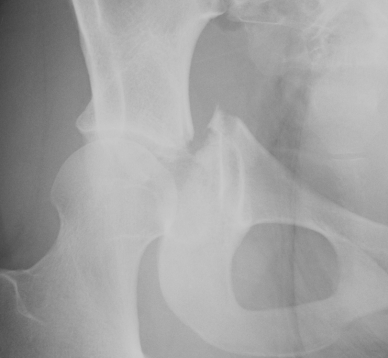

Radiographic factors

1. Articular step < 2mm

2. Weight bearing roof intact

- Matta Roof > 45o

- CT subchondral roof 10 mm

3. Congruent reduction

4. Stable < 40% posterior wall fracture